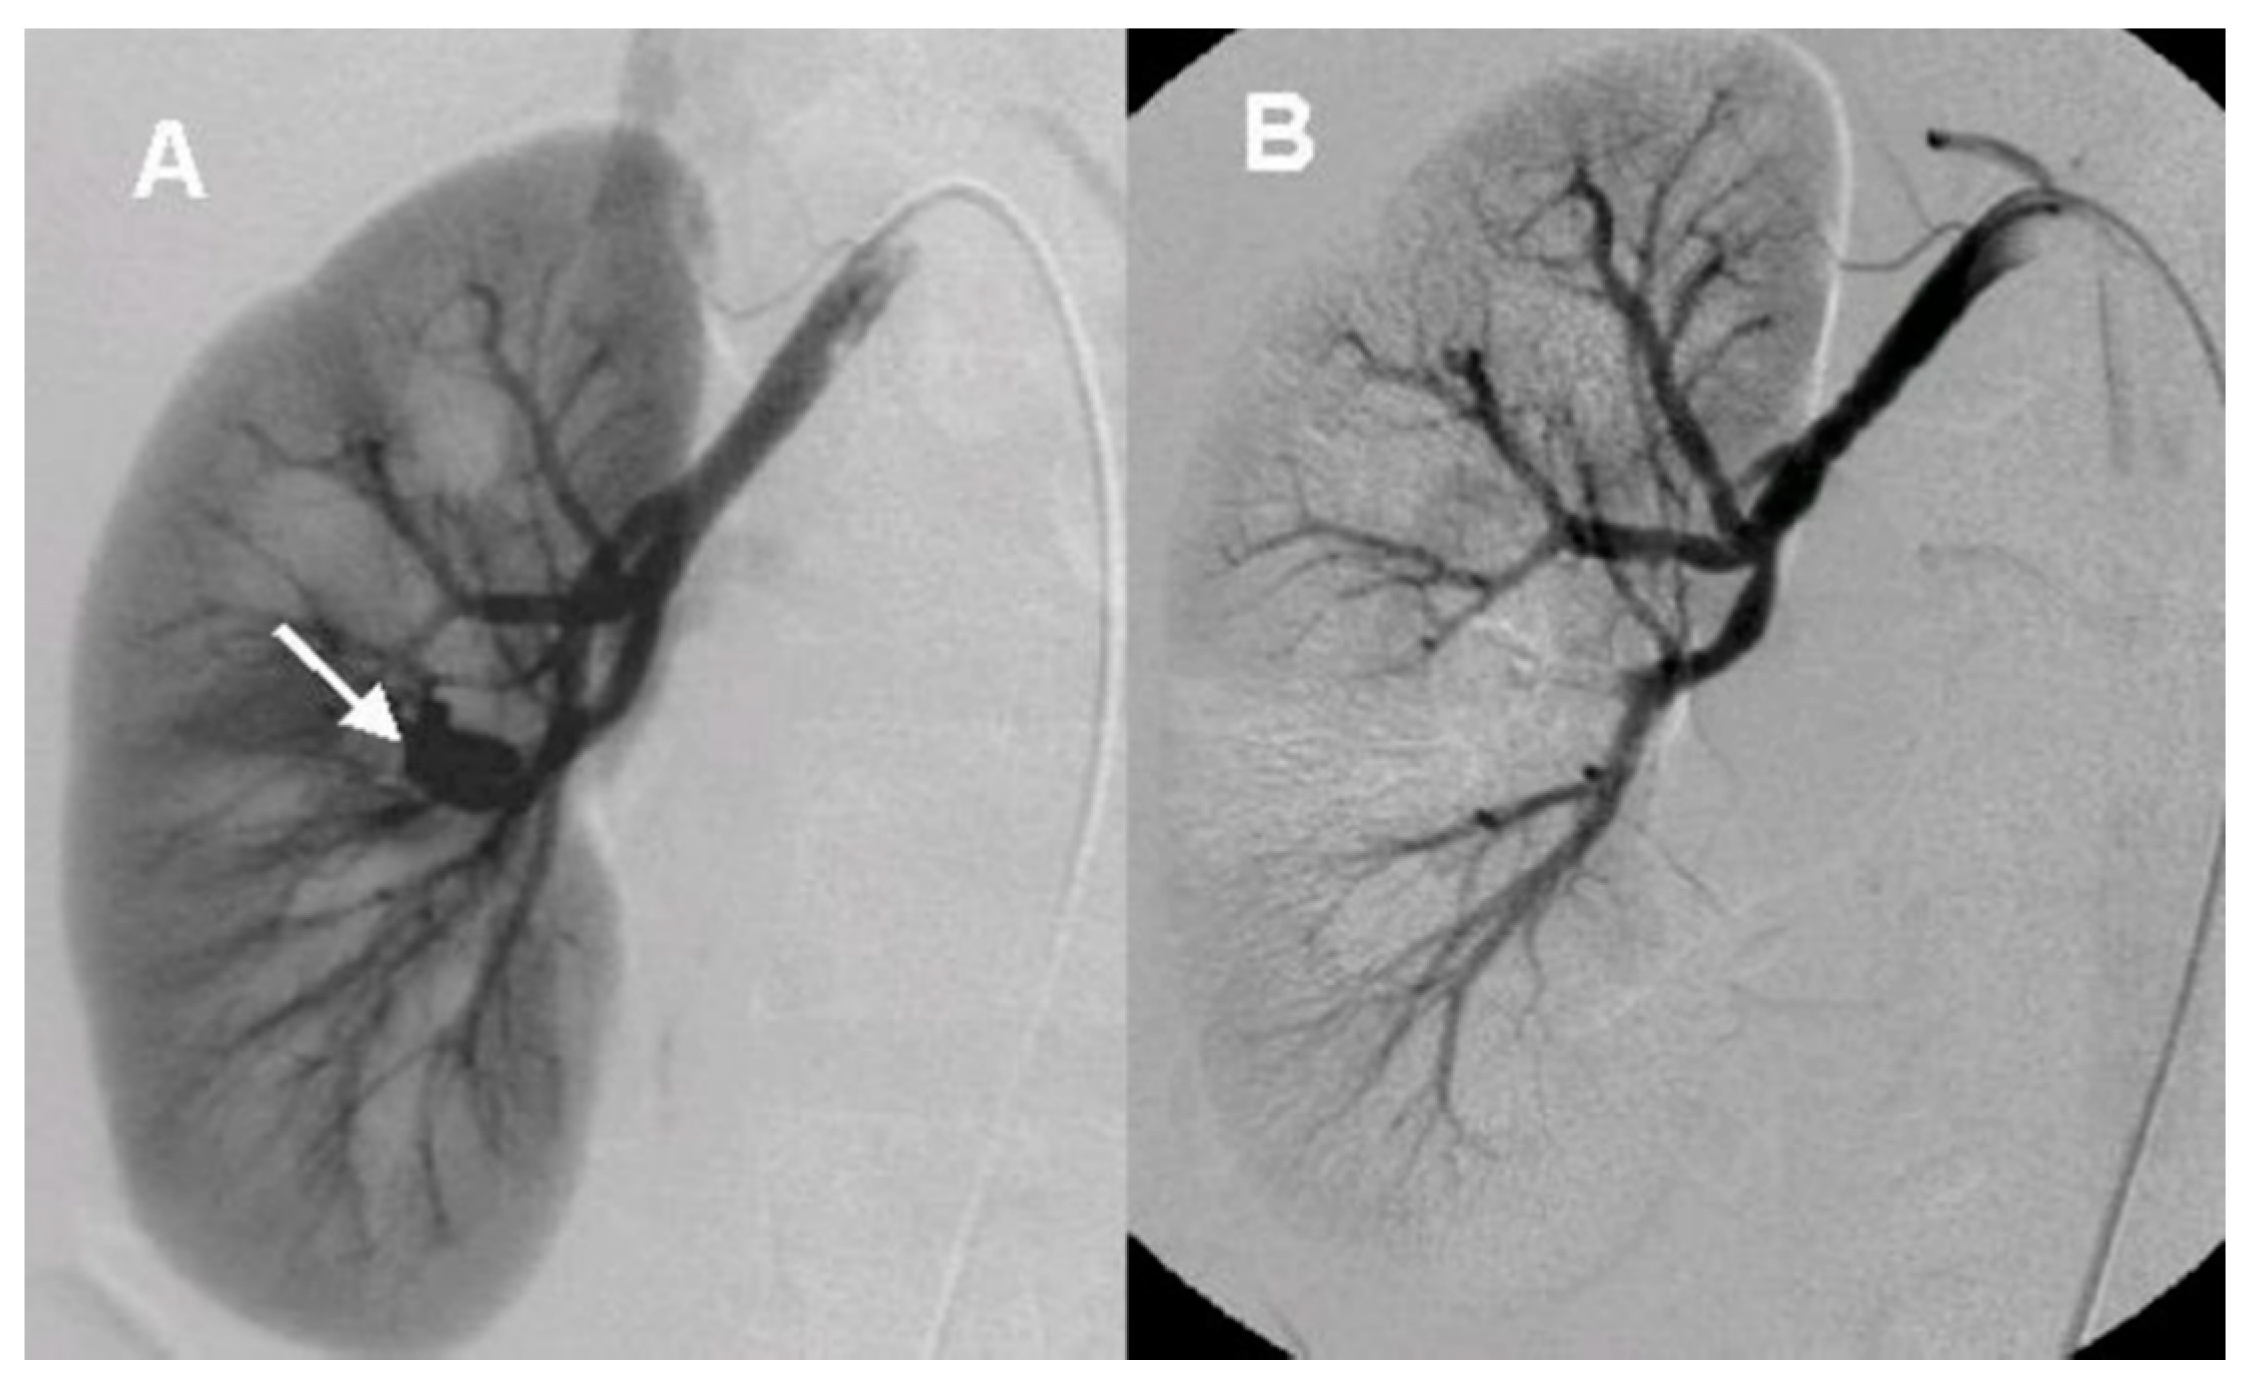

After the initial lab test and imaging study, all patients underwent diagnostic renal angiography for suspicious signs or symptoms such as persistent hematuria, flank pain, hydronephrosis, hematoma in renal pelvis, or hematuria from ureteral orifice on cystoscopy. Angiographic findings showed tortuous vascular communications or aneurysmal dilation with early venous drainage (Figure 2 and Figure 3).

Figure 2. The angiographic findings of idiopathic arteriovenous malformation (A). Renal angiography shows aneurysmal deformity (arrow) with early venous drainage at mid-upper portion (B). Anterosuperior segmental artery was embolized with mixture of 99% ethanol and lipiodol 2 mL.